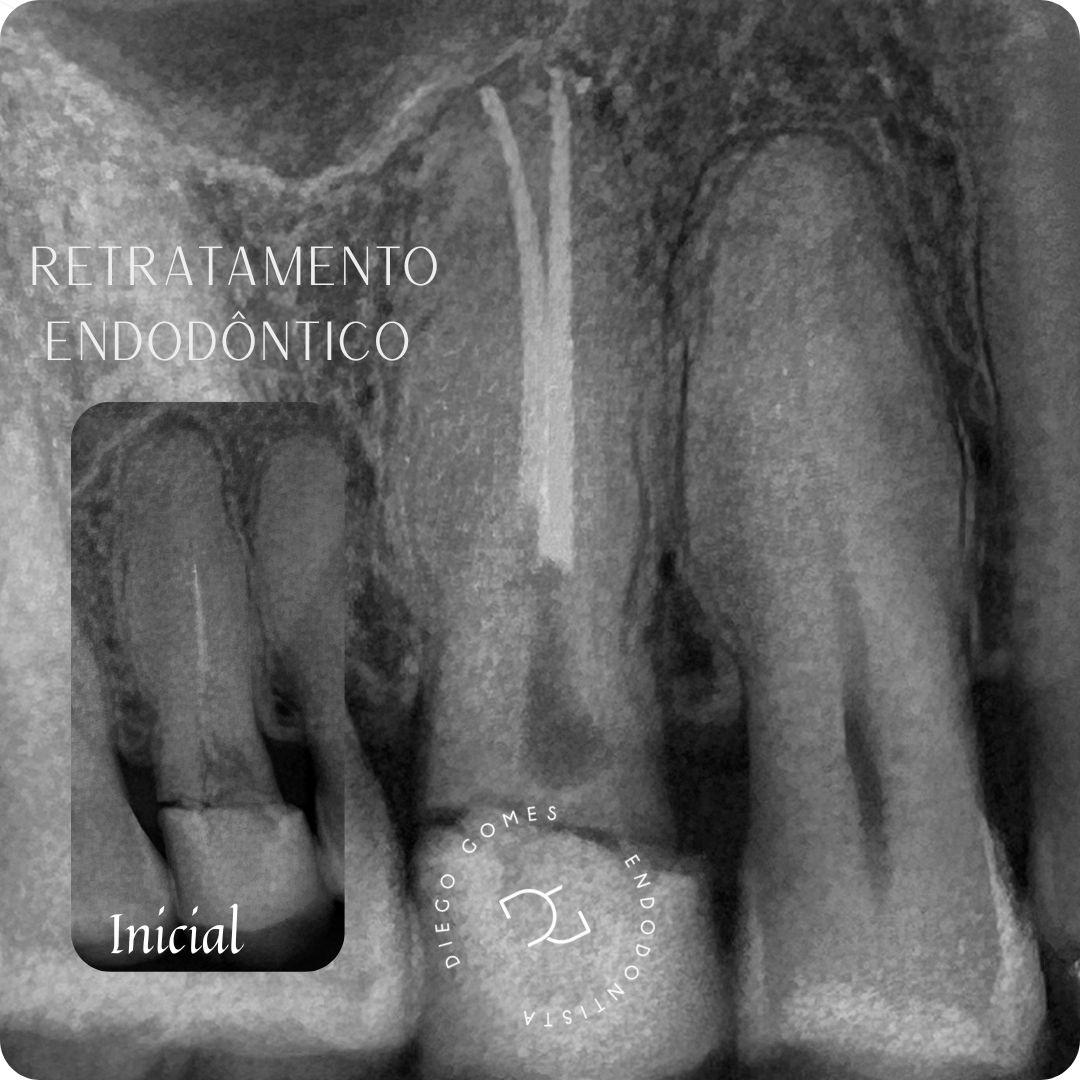

● Tratamento e retratamento de canal